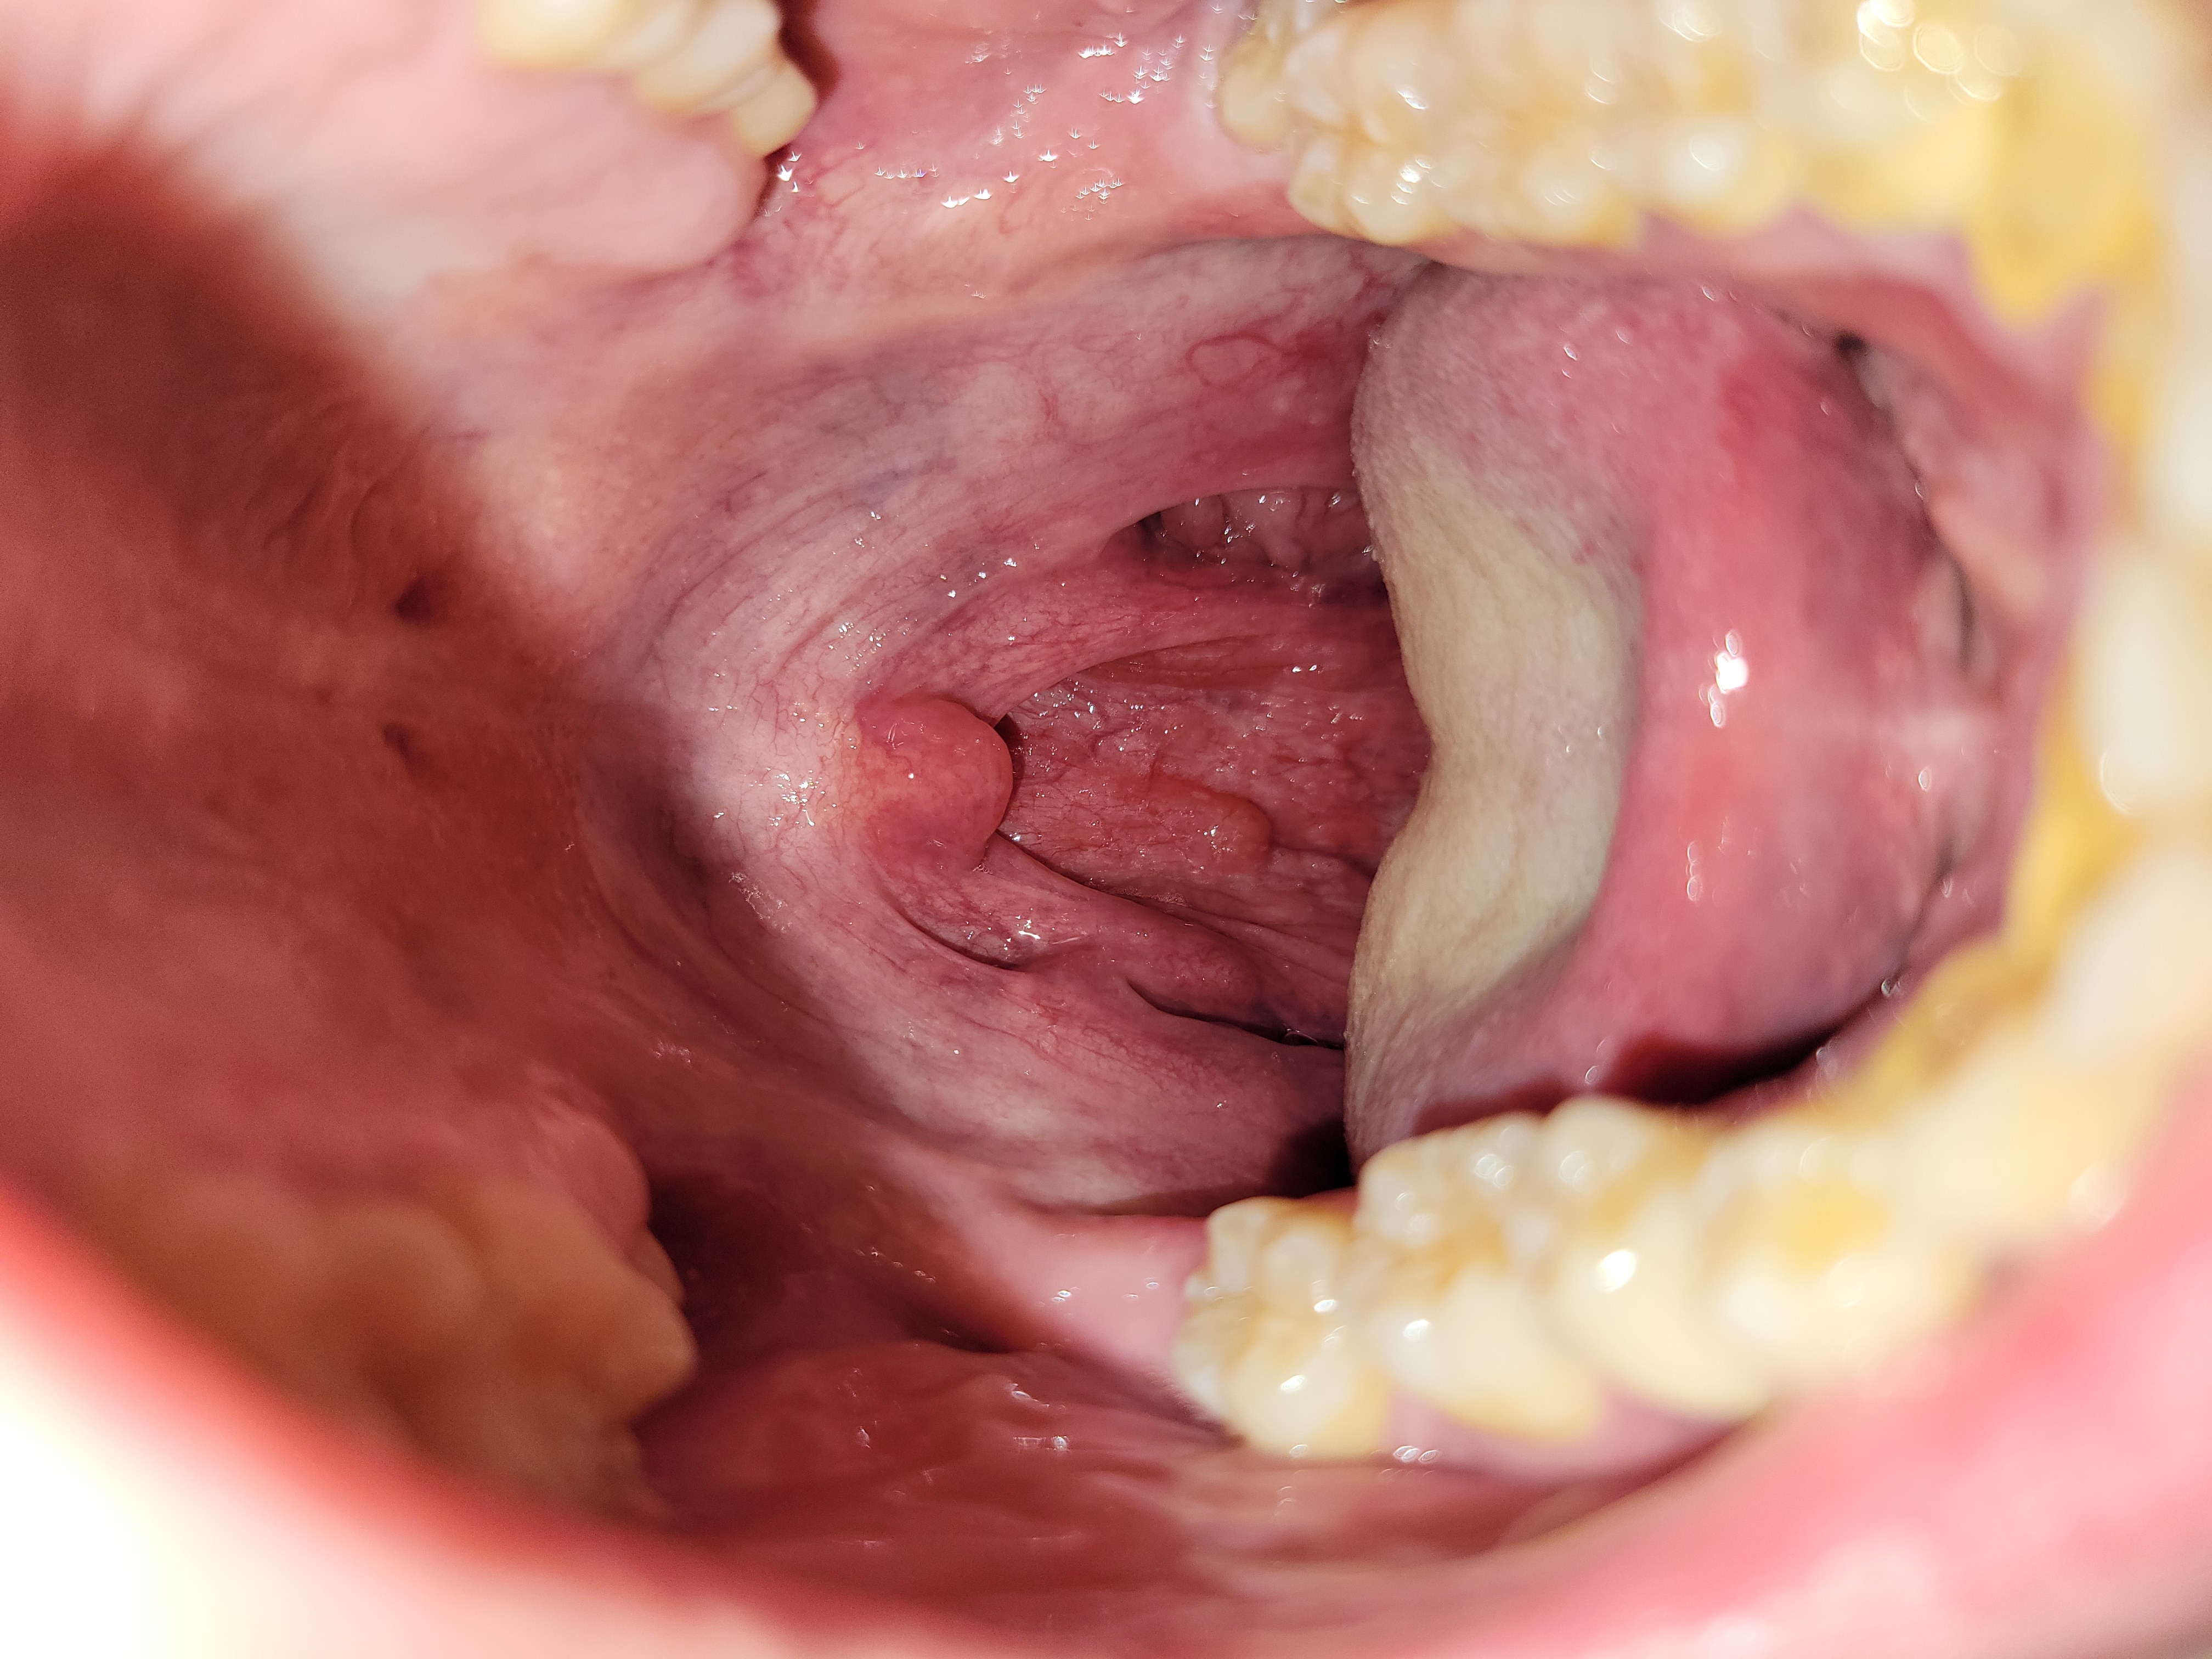

Họng sưng đỏ, chỉ hơi đau họng, có đờm nhiều trong đờm khạc có vài tia máu

Dạ mấy nay họng em có hơi đau em có uống thuốc đau họng ạ nhưng sáng dậy thì vẫn khạc có đờm, đờm lỏng có màu vàng sẫm với trong đó có lẫn vài tia máu. Em xem họng thì thấy họng đỏ như hình ạ. Em bị khoảng gần 4 ngày rồi ạ không biết là em bị gì với cần uống thuốc gì ạ bác sĩ